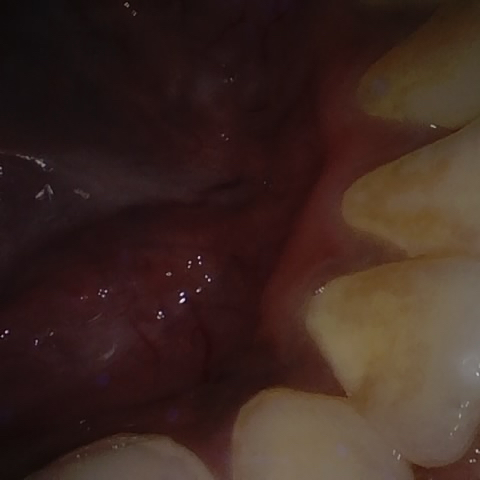

Annotated as "Good"